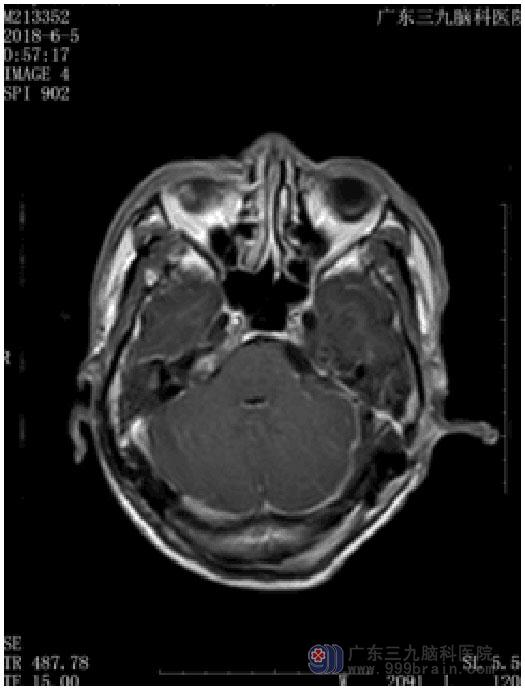

陈先生同意手术治疗,由鲁明主任主刀,在全麻下取乙状窦后入路,确定肿瘤位置,显微镜下分块将肿瘤全切,中后组颅神经保留完整,术程顺利,术后恢复很快,已满意出院。